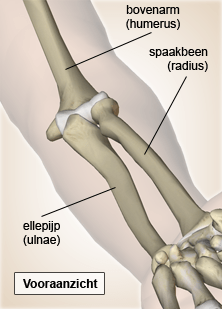

Elleboog